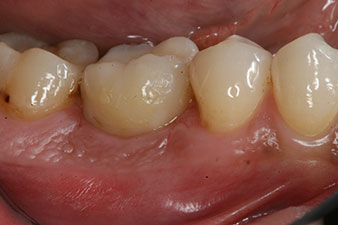

Abformung

Abb. 8: Es folgt die Abformung für die definitive Krone.

Damit konnten eine erfolgreiche Osseointegration und ausreichende biologische Stabilität dokumentiert werden, die eine Abformung in derselben Sitzung erlaubte.

Die Abschlussbilder zeigen die verschraubte monolithische Kompositkrone in situ und die Röntgenkontrolle (Abb. 9 und 10) (6).